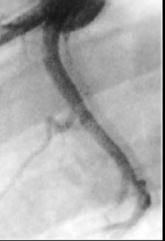

A